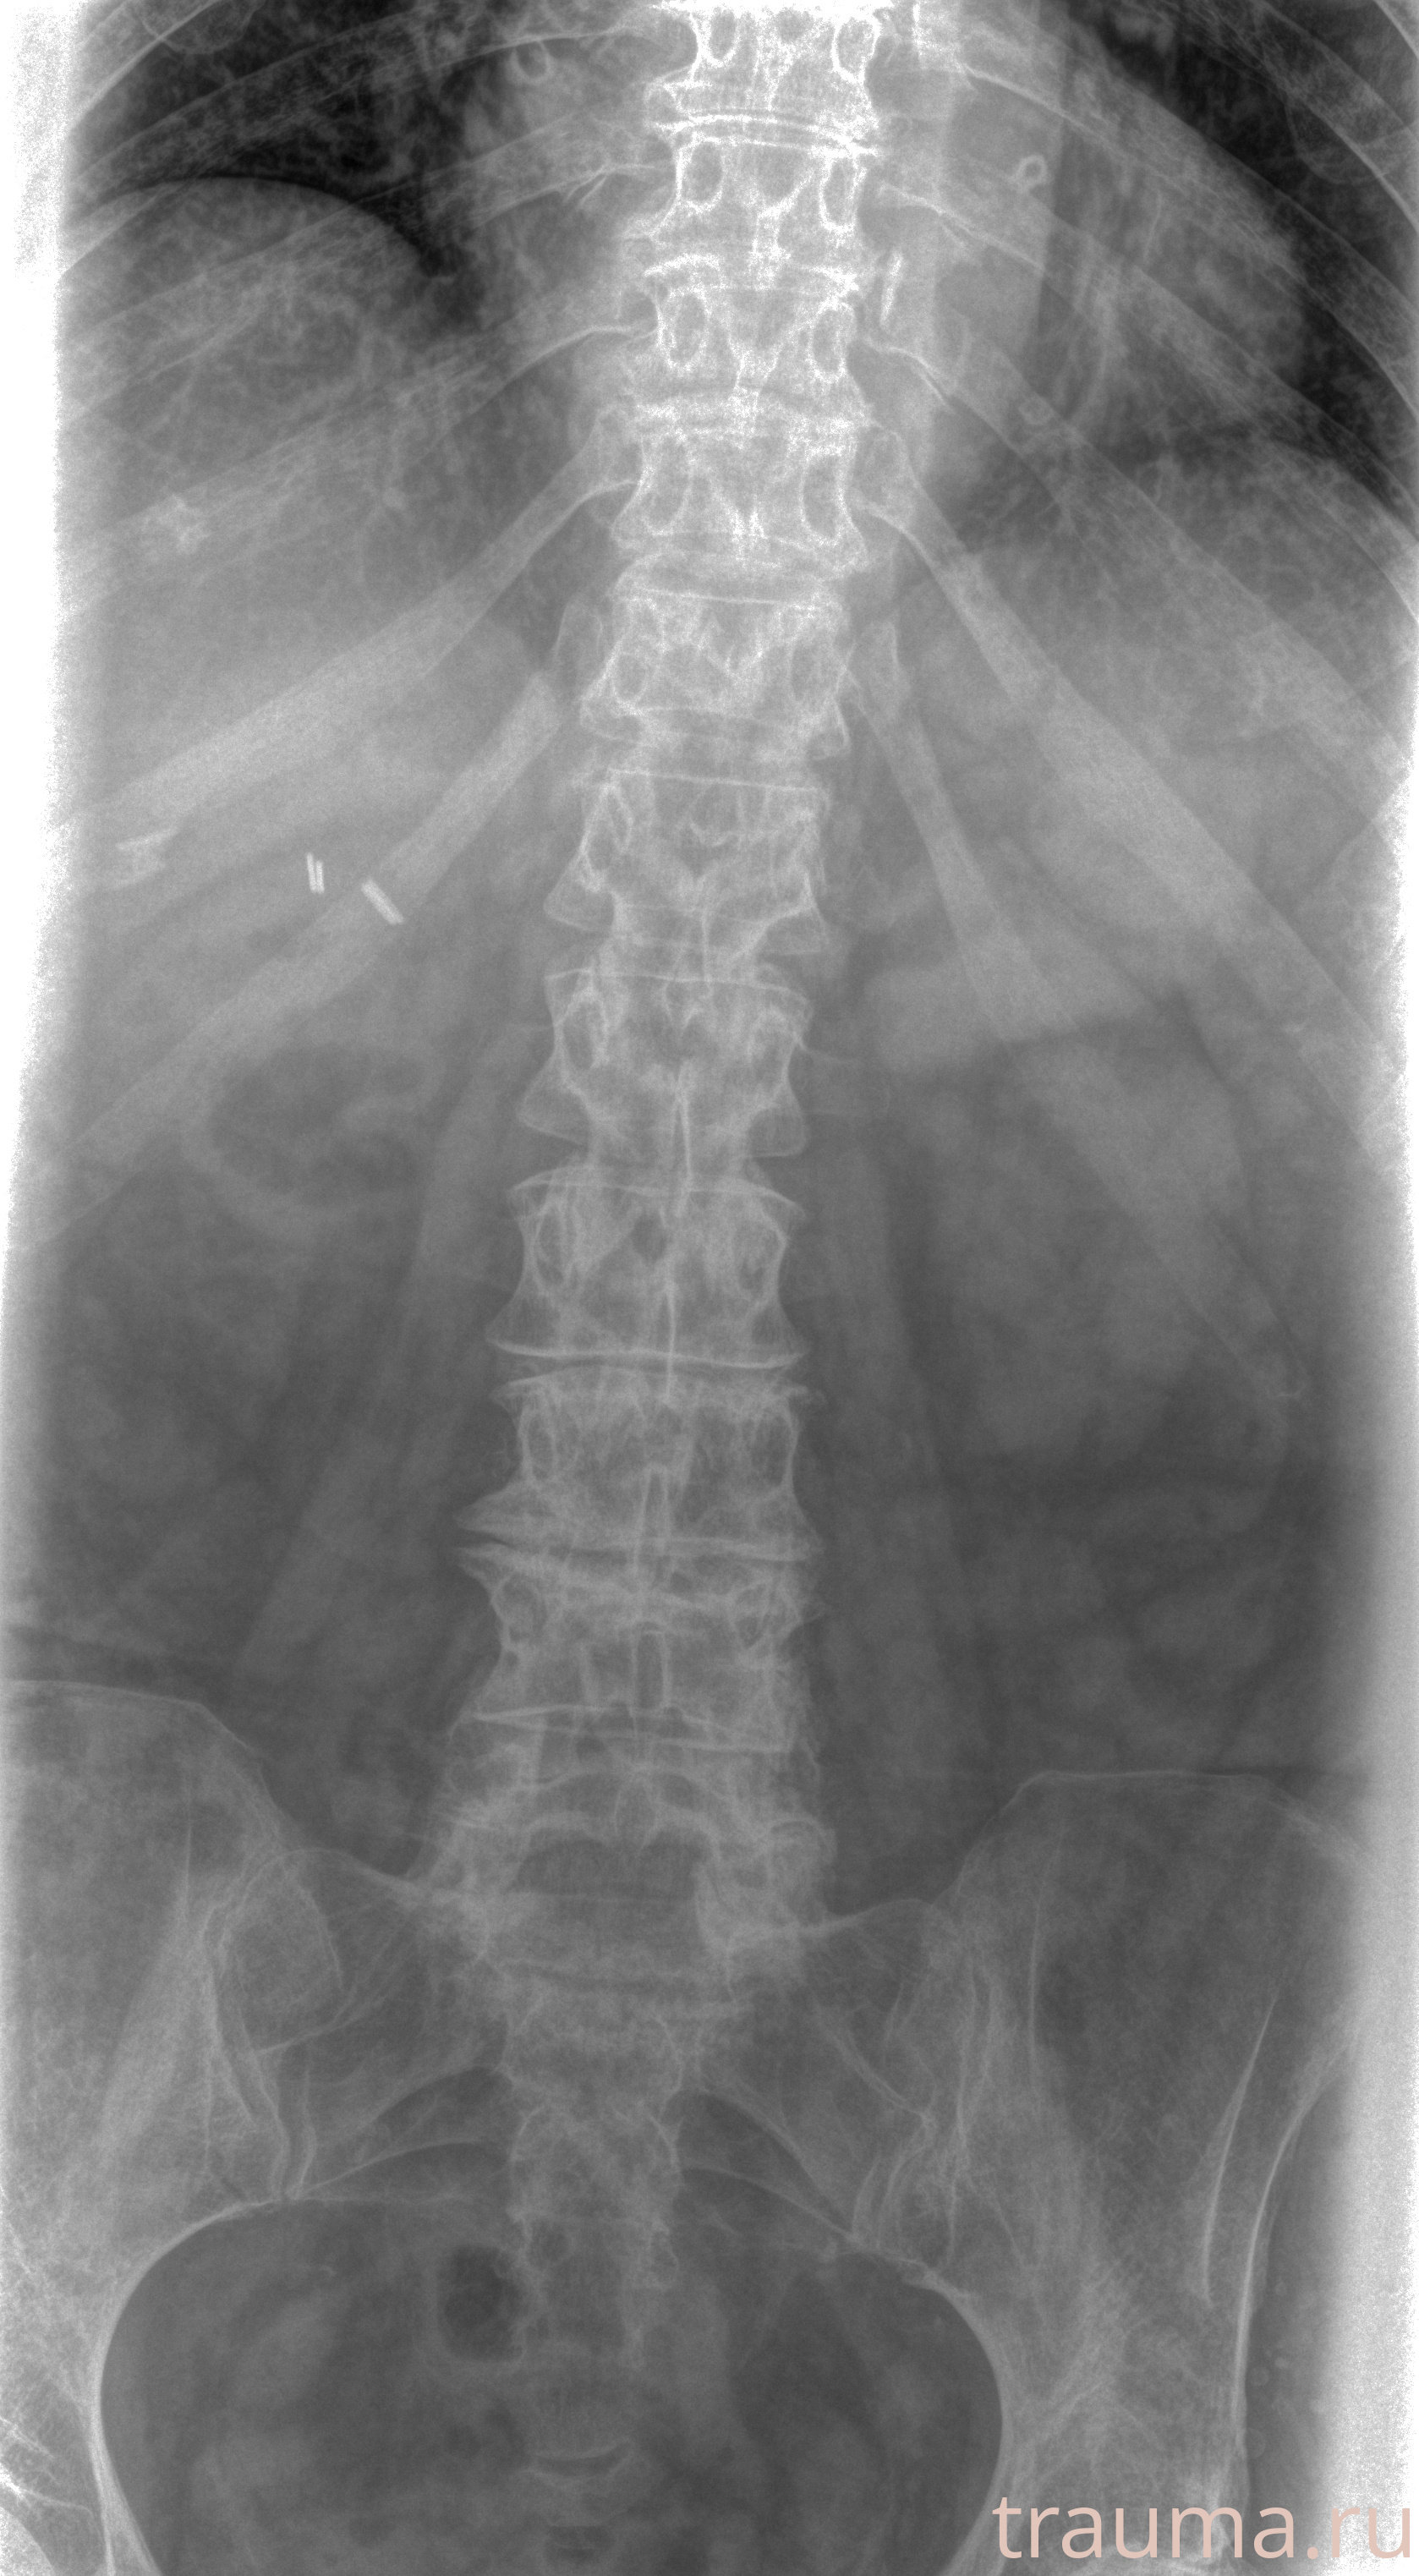

Рентгенограммы

Рентген на дому: по вашему адресу приезжает врач-рентгенолог, травматолог-ортопед с мобильным рентгеновским аппаратом, проводит диагностику травмы или заболевания, делает необходимые рентгенограммы, дает рекомендации по дальнейшему лечению. Получить качественные снимки в домашних условиях возможно благодаря уникальной методике, разработанной МосРентген Центром для института  Склифосовского